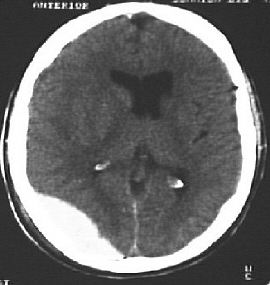

1. You are asked to examine the fundi of a baby with suspected

non-accidental injury and find the above appearance.

2. The paediatrician suspects shaken baby syndrome and order some

radiological investigations. The following pictures are consistent

with the suspicion: